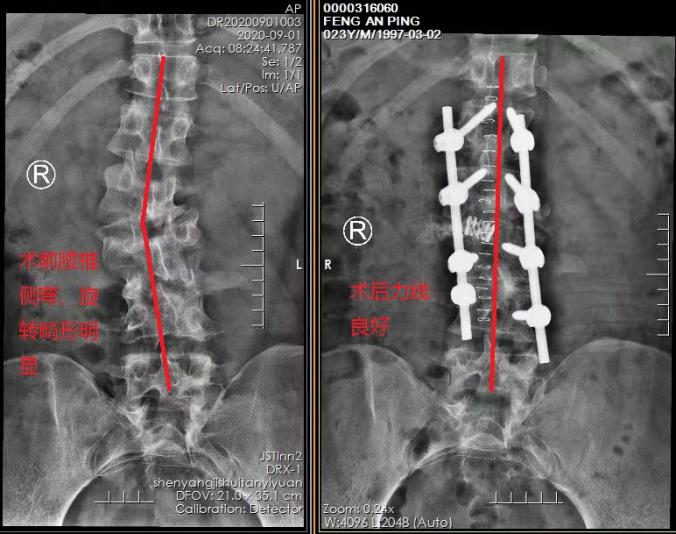

医院脊柱外科主任、北京积水潭医院驻派专家行勇刚为小平进行了详细查体。"通过相关影像检查来看,患者患有'先天性半椎体畸形、先天性马蹄内翻足'。左下肢无力、腰部疼痛感加重是由于先天性半椎体畸形逐渐向椎管内压迫,造成腰椎管狭窄、神经受到压迫,需要尽快进行脊柱矫形手术。"行勇刚主任介绍说。

这样高难度的手术对医生及其团队的技术水平极高的要求。最终,经过充分的术前准备,在麻醉科的配合下,行勇刚主任带领脊柱外科团队历经6小时精心手术,成功为小平施行腰椎截骨矫形手术(腰椎板减压、腰椎半椎体切除、椎间盘切除、椎弓根钉内固定、MESH植入、植骨融合术)。手术过程顺利,患者生命体征平稳,这场高难度挑战取得了完美成功!